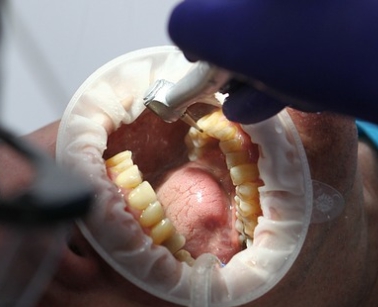

치아 뜻과 이해하기

치아는 사람이나 동물의 입 안에 있는 단단한 구조물로, 음식을 씹고, 발음을 도우며, 얼굴의 형태를 유지하는 중요한 역할을 합니다. 흔히 이(齒)라고도 불리며, 치아는 생물의 소화 과정에서 첫 번째로 작용하는 기관입니다.

치아의 구조

치아는 크게 세 부분으로 나뉩니다:

- 치관(齒冠):

입 안에서 보이는 부분으로, 음식물을 직접 부수고 씹는 역할을 합니다.- 법랑질: 치아 표면을 덮고 있는 가장 단단한 조직.

- 상아질: 법랑질 아래에 위치하며, 치아의 주된 구조를 이룹니다.

- 치경(齒頸):

잇몸과 접촉하는 부분으로, 치아와 잇몸을 연결하는 역할을 합니다. - 치근(齒根):

잇몸 안쪽에 박혀 있는 부분으로, 치아를 턱뼈에 고정시키며 안정성을 제공합니다.- 치근은 치수(신경과 혈관이 모여 있는 부분)를 보호합니다.